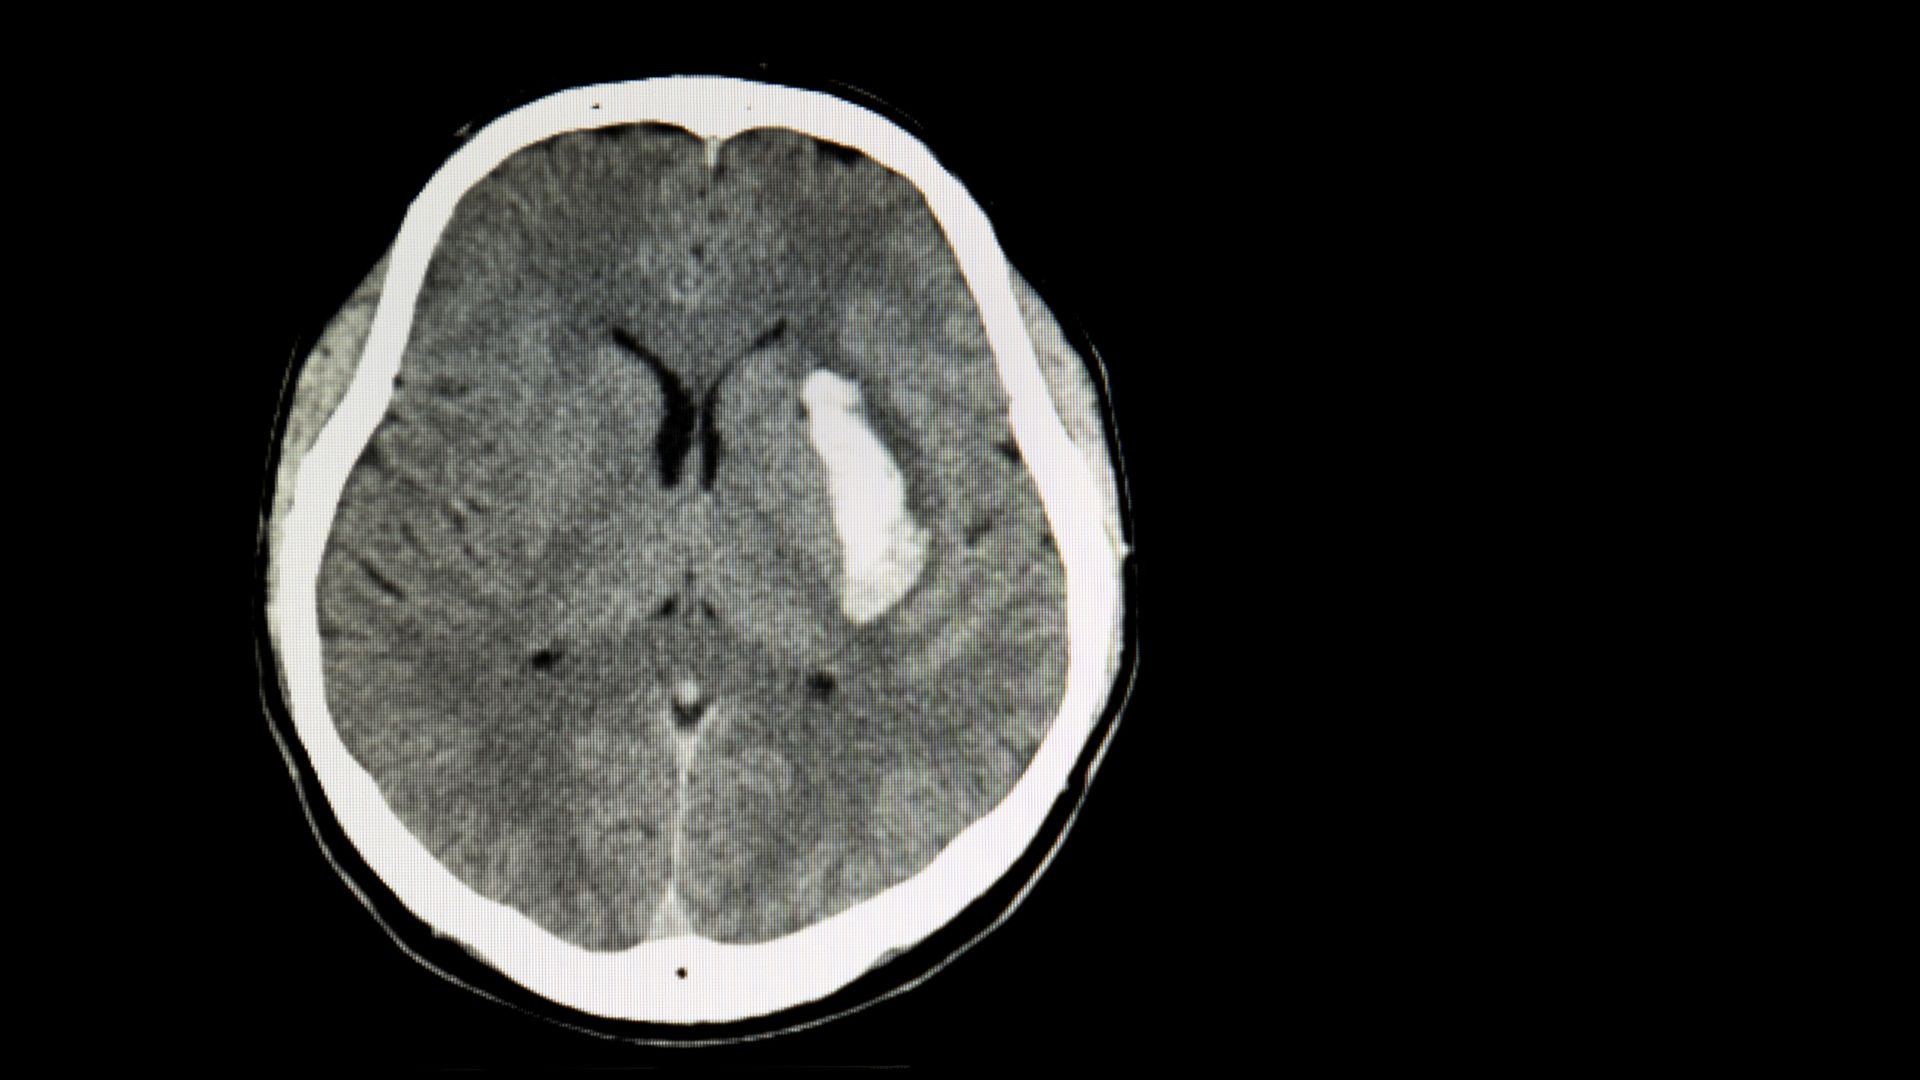

- CT não: Thường dùng trong cấp cứu để phát hiện xuất huyết nội sọ nhanh chóng.

- Xuất huyết nội sọ: Đây là biến chứng nguy hiểm nhất, đặc biệt ở dị dạng động - tĩnh mạch. Thành mạch bất thường, mỏng và chịu áp lực cao dễ bị vỡ, gây xuất huyết nhu mô não, xuất huyết dưới nhện hoặc trong não thất. Tình trạng này có thể dẫn đến tăng áp lực nội sọ, tổn thương não cấp tính, hôn mê hoặc tử vong.